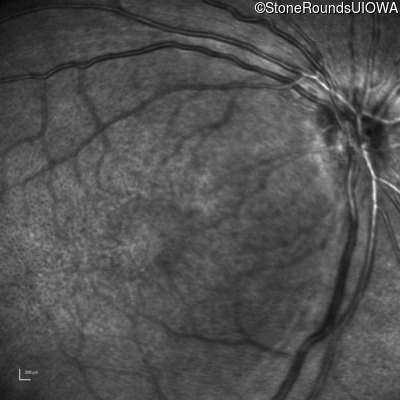

XL Retinoschisis (IIIB1)

Age at visit: 6 years

OD OS

This 6 year old boy began sitting very close to the television at age 2.

Diagnosis & molecular findings

XL Retinoschisis RS1 Tyr93Stop TAT>TAG   XL